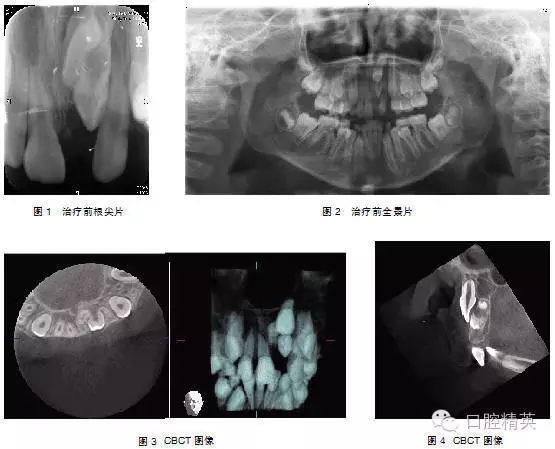

典型病例3:患者,男,11歲,因—1未萌來我院就診(圖1)。

檢查: |1未萌,1|全萌,1|2之間間隙為5mm。X線片示: |1骨內(nèi)埋伏,倒置,埋伏牙倒置角度在130°,牙冠的腭側(cè)面向外,稍彎根,1| 牙根基本形成(圖2~4)。

處理:行外科開窗+正畸牽引治療,6個(gè)月后破齦萌出,連續(xù)牽引,12個(gè)月后到位(圖5~7)。